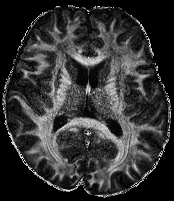

3.2.3 Example 2: Diffusion-weighted MRI (dMRI)

DMRI is an important MRI technique to study the neural architecture and connectivity of the brain. It is based on obtaining multiple 3333-dimensional diffusion-weighted images to investigate the water diffusivity along various directions, being clinically important especially for the investigation of brain disorders, see e.g. (citep \@BBN(Shenton et al., 2012)). However, low signal-to-noise ratio and acquisition time limit the spatial resolution of dMRI and therefore its usage is currently mainly restricted to medium-to-large white matter structures, whereas very small cortical or sub-cortical regions cannot be traced accurately. To overcome this, several methods for increasing the spatial resolution of dMRI have been introcuded, see e.g. (citep \@BBN(Dyrby et al., 2014; Van Steenkiste et al., 2016; Grieve and Maller, 2017)).

Here, we study image data from an acquisition and reconstruction scheme for obtaining high spatial resolution dMRI images using multiple low resolution images, cf. (citep \@BBN(Ning et al., 2016)). The suggested method combines the concepts of compressed sensing and super-resolution to reconstruct high resolution diffusion data while allowing faster scan time. The data is visualized via the fractional anisotropy (FA) measures computed using diffusion tensor imaging (citep \@BBN(Basser, Mattiello, and LeBihan, 1994)).

The data from a human subject was acquired from a MGH connectome 3T scanner. Three thick-slice diffusion weighted imaging (DWI) volumes with voxel size 0.9×0.9×2.7mm30.90.92.7𝑚superscript𝑚30.9\times 0.9\times 2.7mm^{3}0.9 × 0.9 × 2.7 italic_m italic_m start_POSTSUPERSCRIPT 3 end_POSTSUPERSCRIPT, TE/TR = 84/7600ms847600𝑚𝑠84/7600ms84 / 7600 italic_m italic_s and 60606060 gradient directions at b=2000s/mm2𝑏2000𝑠𝑚superscript𝑚2b=2000s/mm^{2}italic_b = 2000 italic_s / italic_m italic_m start_POSTSUPERSCRIPT 2 end_POSTSUPERSCRIPT. A separate low-resolution isotropic DWI with a spatial resolution of 1.8×1.8×1.8mm31.81.81.8𝑚superscript𝑚31.8\times 1.8\times 1.8mm^{3}1.8 × 1.8 × 1.8 italic_m italic_m start_POSTSUPERSCRIPT 3 end_POSTSUPERSCRIPT and with 60606060 gradient directions at b=2000s/mm2𝑏2000𝑠𝑚superscript𝑚2b=2000s/mm^{2}italic_b = 2000 italic_s / italic_m italic_m start_POSTSUPERSCRIPT 2 end_POSTSUPERSCRIPT.

The super resolution image in 6(a), serving as a reference here, was obtained using the super-resolution reconstruction technique that combines multiple thick-slice DWI with all 60 diffusion directions into a high-resolution image, cf. (citep \@BBN(Ramos-Llordén et al., 2020)). This technique yields a high quality image with good detail preservation, but takes much longer scan time than the standard upsampling method in 6(c), where the FA map of the low-resolution data was up-sampled using 3DSlicer (citep \@BBN(Fedorov et al., 2012)) to the higher resolution.

The image in 6(b), cf. (citep \@BBN(Ning et al., 2016)), was obtained using a combined super-resolution reconstruction, compressive sensing, and spatial regularization techniques with thick-slice images, where each thick-slice DWI has a different set of 20202020 diffusion gradient directions, saving indispensable scan time. The advanced method yields a much higher visual quality image than 6(c), preserving more anatomical details.

Refer to caption

(a) Reference

(b) (17.62, 0.57, 0.19)

(c) (18.23, 0.58, 0.26)

Figure 6: Visualized FA images obtained from diffusion MRI with super-resolution reconstructions. The up-sampled image (c) with lower resolution is wrongly judged to have better quality than the high-resolution reconstruction (b) by PSNR and SSIM, LPIPS judges this task correctly.

FR-IQA mismatch

We can see in Figure 6 that PSNR and SSIM misjudge the visual quality of the high-resolution reconstruction in (b) in comparison to the up-sampled image in (c). The image is per default more blurry and does not provide sufficient anatomical details and therefore offers worse visual quality than the reconstruction in (b). LPIPS yields more sufficient results in this example, and correctly attributes (c) a higher quality error.

In this example it has to be noted that the computed IQA numbers are generally quite low, because the resulting FA images do not necessarily have the same range or distribution as the reference image. Therefore, in order to compare the reconstruction quality directly, this task generally benefits from NR-IQA evaluation.